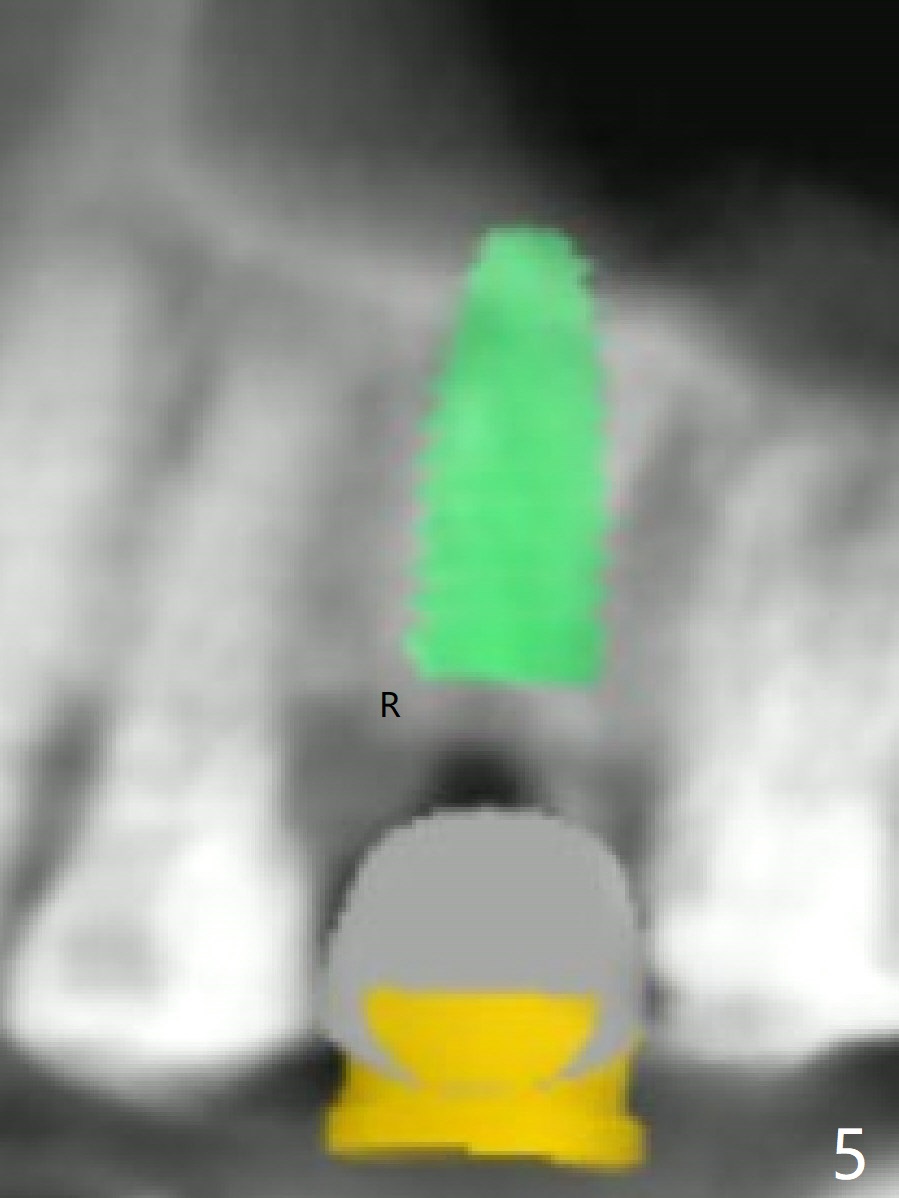

A 49-year-old woman has loose splinted crowns between #13 and 14. After removal of the crowns, the tooth #13 is found non-salvageable (Fig.1). A 4 or 4.5 x 8.5 or 10 mm implant should be able to achieve primary stability because of engagement of the implant into the mesial and distal walls of the socket and the sinus floor. Splinted provisional should provide with additional retention. There is no much need for socket shield, since there is no mesial or distal crestal bone loss (associated with food impaction). If the crown is short, there is no concern about buccal gingival recession. In fact the mesial papilla is more apical than the distal one (Fig.2 *), corresponding to the more apical crest (Fig.3 *). To prevent further mesial crestal loss post extraction, socket shield seems necessary. There appears that the implant is placed distal enough so that a small portion of the mesial root (Fig.4,5 R) is able to be saved. Fig.6 is the occlusal view of the residual root of the tooth #13. The mesial sheath will be kept (Fig.7,8, as compared to Fig.3).